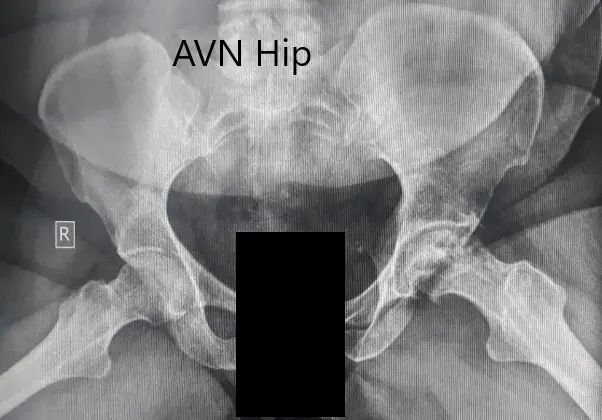

An X-Ray was obtained suggesting severe loss of joint space with acetabulum changes in the left hip. There was a loss of spherical contour of the left hip. Sclerosis and subchondral cysts were present in the left hip with a collapse.

Preoperative X-ray of the pelvis with both hips in the frog-legged lateral view showing AVN changes in the left hip.